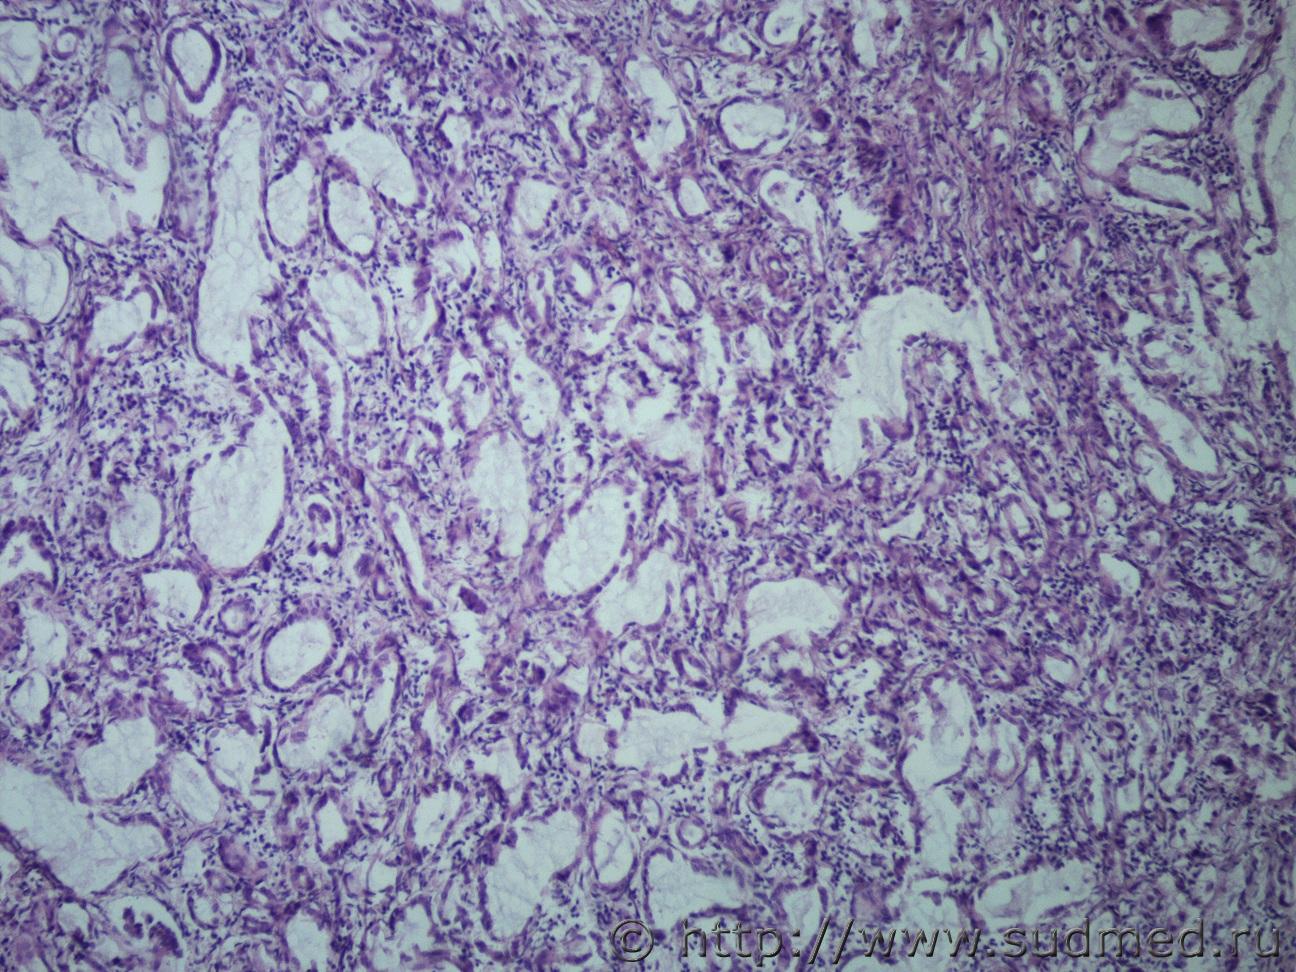

Ув. коллеги, сегодня в рубрике опухоль поджелудочной железы с метастазами в легкие. Муж, 80лет.

Легкие Судебная медицина - Прикрепленное изображениеСудебная медицина - Прикрепленное изображениеСудебная медицина - Прикрепленное изображение ПЖ Судебная медицина - Прикрепленное изображениеСудебная медицина - Прикрепленное изображениеСудебная медицина - Прикрепленное изображениеСудебная медицина - Прикрепленное изображение

Похоже на муцинозную цистаденокарциному? В легких очень красивый эпителий, а вот в поджелудочной такого эпителия очень мало(((

Похоже на муцинозную цистаденокарциному?

Да.

В гист.Акте печатайте без "цист". Просто, "муцинозная аденокарцинома".